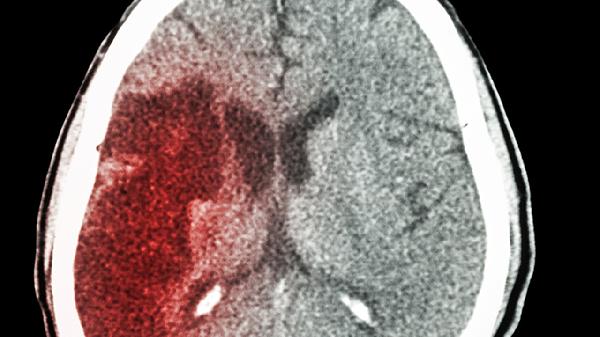

深夜的急诊室总是充满故事,58岁的老张被救护车送来时,半边身体已经不能动了。值班医生看了一眼监护仪:"又是典型的餐后脑梗。"这样的场景几乎每周都在重演,而很多悲剧其实就藏在晚饭后的那些习惯里。